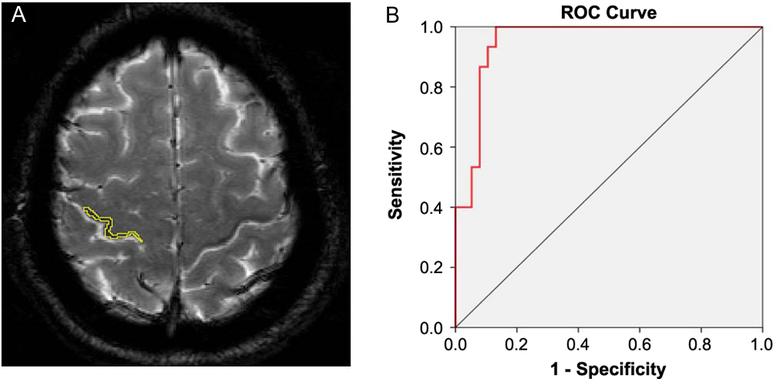

Figure 2: (A) Contour detection of the right “black ribbon” (BR) to measure signal attenuation. (B) Receiver operating characteristic curve of signal intensity showing an area under the curve (AUC) of 0.951.

BR Sign Measurement

Visual analysis of the BR yielded good intra-rater and inter-rater kappa values that ranged from 0.69 to 0.98. Visual interpretations were complemented by measurements of signal intensity in the delineated area of the sign (Figure 2A) and a ribbon model placed over the precentral region when signal attenuation was not distinguishable. A quantitative analysis of signal attenuation confirmed enhanced paramagnetic effect in 33 patients with ALS (91.66%). Patients displaying the sign presented a BR in multiple image slices (2–9 axial cuts). Inter-rater correlation for these measurements was 0.953 (p < 0.001); sample results from two observers (Y.A. and J.M.) are shown in Figure 1A. The area of hypointensity obtained by multiplying the area of each inner slice (i.e., excluding the two edges) by 3 mm yielded a mean (± standard error of the mean) area of 75.4 ± 9.0 mm3 in the left hemisphere and 84.0 ± 9.0 mm3 in the right hemisphere. The 3D reconstruction model shown in Figure 3 was used to design and position a BR paradigm ROI for further measurements, especially when the sign was discrete or invisible (e.g., in control subjects). Signal intensity under the cut-off value of 83 AUSI was able to diagnose ALS with 97% accuracy, 92% sensitivity, 93% specificity, and a predictive positive value of 0.97. The area under the receiver operating characteristic (ROC) curve of 0.95 is presented in Figure 2B.

In the whole cohort, 34 subjects (33 patients and 1 control subject) exhibited the BR sign in the posterior bank of the motor cortex. A quantitative analysis confirmed that patients with ALS had significantly higher paramagnetic effect in this region, and a receiver operating characteristic analysis indicated that a cut-off value of 83 AUSI in the posterior bank of the motor cortex had an AUC of 0.95 (p < 0.001) for discriminating patients with ALS from control subjects. Additionally, there was a reliable correlation between muscle strength in the contralateral upper extremities and signal intensity of the BR (Figure 4A). Respiratory forced vital capacity and body mass index showed significant relationships with signal attenuation in the BR area with a Pearson’s coefficient of 0.355 (p = 0.036) and 0.363 (p = 0.010), respectively. Patient-scored quality of life was only correlated with deterioration index (Pearson’s coefficient = 0.506, p = 0.002). There was a marginal correlation between measured BR area and body mass index (p = 0.044), while BR signal intensities in both precentral gyri were significantly correlated with forced vital capacity (Spearman r = 0.380, p = 0.020, in the right hemisphere and r = 0.33, p = 0.047, in the left hemisphere).